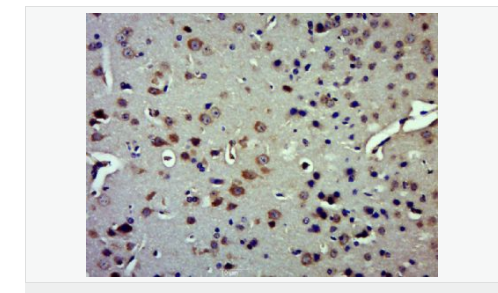

| 產(chǎn)品應用 | WB=1:500-2000 ELISA=1:5000-10000 IHC-P=1:100-500 IHC-F=1:100-500 IF=1:100-500 (石蠟切片需做抗原修復) not yet tested in other applications. optimal dilutions/concentrations should be determined by the end user. |

| 產(chǎn)品介紹 | Insulysin was identified nearly a century ago as an enzyme responsible for the degradation of insulin in cells, although the precise interactions between insulin and insulysin remain elusive. Human insulysin was cloned in 1988, and shown to be a 118 kDa protein that exists primarily as a homodimer, and perhaps also complexed with other molecules. The sequence is well conserved between humans, rats and mice, and the antibody recognizes these species. Insulysin is a metalloproteinase of the clan ME, family M16, which contains an active site HxxEH, a reversal of the canonical HExxH zinc binding motif. Considered a zinc metalloproteinase, the activity of insulysin can be blocked with EDTA or 1-10 phenanthroline. In addition to the active metalloproteinase domain, insulysin contains a second metalloproteinase site which is considered catalytically inactive, and is thought to assist in substrate binding. Insulysin is most closely related to the bacterial proteinase pitrilysin, (the human orthologue of which appears to be MPRP1) and the mammalian proteinsae nardilysin. Generally thought to be a cytoplasmic protein, insulysin has been isolated from many different tissues and cell lines, and can degrade intact insulin, insulin B chain, glucagon, denatured hemoglobin, alpha amyloid protein, TGF alpha and amylin. Recent work implicates insulysin in clearing beta amyloid plaques from the brain, and has generated much interest in Alzheimer’s disease research. The pH optimum for insulysin is basic, pH 8.5, which also distinguishes it from other metalloproteinases. Function: Plays a role in the cellular breakdown of insulin, IAPP, glucagon, bradykinin, kallidin and other peptides, and thereby plays a role in intercellular peptide signaling. Degrades amyloid formed by APP and IAPP. May play a role in the degradation and clearance of naturally secreted amyloid beta-protein by neurons and microglia. Subunit: Homodimer. Can form higher oligomers. Interacts (via N-terminus) with varicella-zoster virus (VZV) envelope glycoprotein E (via N-terminus); the membrane-associated isoform may function as an entry receptor for this virus. Subcellular Location: Cytoplasm. Cell membrane. Secreted. Note=Present at the cell surface of neuron cells. The membrane-associated isoform is approximately 5 kDa larger than the known cytosolic isoform. Post-translational modifications: The N-terminus is blocked. Similarity: Belongs to the peptidase M16 family. SWISS: P14735 Gene ID: 3416 Database links: Entrez Gene: 3416 Human Entrez Gene: 15925 Mouse Omim: 146680 Human SwissProt: P14735 Human SwissProt: Q9JHR7 Mouse Unigene: 500546 Human Unigene: 28366 Mouse Unigene: 45029 Rat Important Note: This product as supplied is intended for research use only, not for use in human, therapeutic or diagnostic applications. |